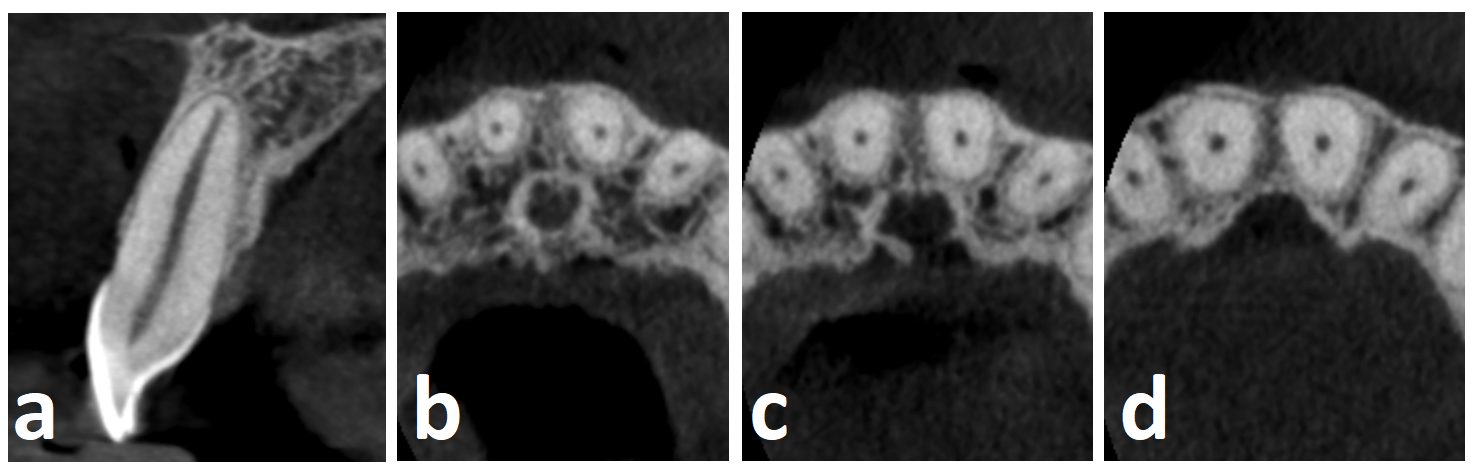

W tym miejscu należy wspomnieć, że zębami jednokorzeniowymi, które posiadają niemal zawsze jeden kanał są zęby przednie szczęki (ryc. 1). Zęby przednie żuchwy, mimo iż są zębami jednokorzeniowymi, bardzo często posiadają dwa kanały. Według badań przeprowadzonych w polskiej populacji dwukanałowe zęby sieczne występowały w 1/3 przypadków, a kły dolne w nieco ponad 10% (ryc. 2) (4). Również dość często dwa kanały można stwierdzić w jednokorzeniowych zębach przedtrzonowych (drugi ząb przedtrzonowy szczęki; zęby przedtrzonowe żuchwy) czy zębach trzonowych (np. w często występującym jednokorzeniowym drugim zębie trzonowym żuchwy). W przypadku tych zębów wykonanie zdjęcia wewnątrzustnego w projekcji skośnej uwidacznia obecność dwóch lub większej liczby kanałów, choć niekiedy (np. zęby sieczne dolne) obrazy zębów mogą na siebie nakładać się uniemożliwiając analizę zdjęcia pod kątem występowania odmiany dwukanałowej. W takim przypadku okazuje się przydatna tomografia komputerowa.

Ryc. 1. CBCT zęba siecznego przyśrodkowego szczęki o typowej morfologii kanału (pojedynczy kanał): a. przekrój strzałowy; b. przekroje poprzeczne korzeni zębów siecznych szczęki wykonane w obrębie odcinków wierzchołkowych; c. przekroje poprzeczne korzeni zębów siecznych szczęki wykonane w obrębie odcinków środkowych; d. przekroje poprzeczne korzeni zębów siecznych szczęki wykonane w obrębie odcinków koronowych.